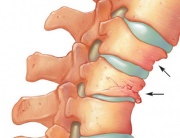

If osteoporosis is not prevented or treated, it can evolve without any symptoms until a bone fracture occurs – most probably a hip, vertebral or wrist fracture. A hip fracture always requires hospitalization and a major surgical intervention. These fractures generally cause significant disabilities and sometimes even death, if left untreated. Vertebral fractures may cause height loss, severe back pain and the deformation of the spine.

Osteoporosis fractures may lead to a change of posture (e.g., the curving of the back or the formation of a kyphosis), the weakening of the muscles, the height loss, the deformation of the spine. Fractures can cause chronic pain, lack of independence and even the premature death. A person with an osteoporotic fracture is admitted in the hospitals in Australia every 5-6 minutes. This interval is expected to drop to 3-4 minutes by 2021, with the ageing of the population and the increase in the number of osteoporotic fractures. Approximately 50% of the people suffering from an osteoporotic fracture will experience another one, and the fracture risk increases with every new fracture; a phenomenon called the cascade effect.

The cascade effect means that women who experienced a vertebral fracture have 4 times the risk of a new fracture during the following year as compared to women who never had an osteoporotic fracture. People who suffered 2 or more osteoporotic fractures have a 9 times higher risk of new fractures, which can be 11 or even more times higher in the case of people suffering from 3 or more fractures.

Approximately 65% of the vertebral fracture risks are not identified and treated, even most of them cause pain and a certain degree of physical disability. In general, people associate vertebral fracture symptoms – back pain, height loss, spinal deformation – to the age. However, most osteoporotic fractures can be prevented, or at least the risk of a new fracture can be significantly reduced. In order to counter this cascade effect, it is essential that osteoporotic fractures be identified and treated as soon as possible.